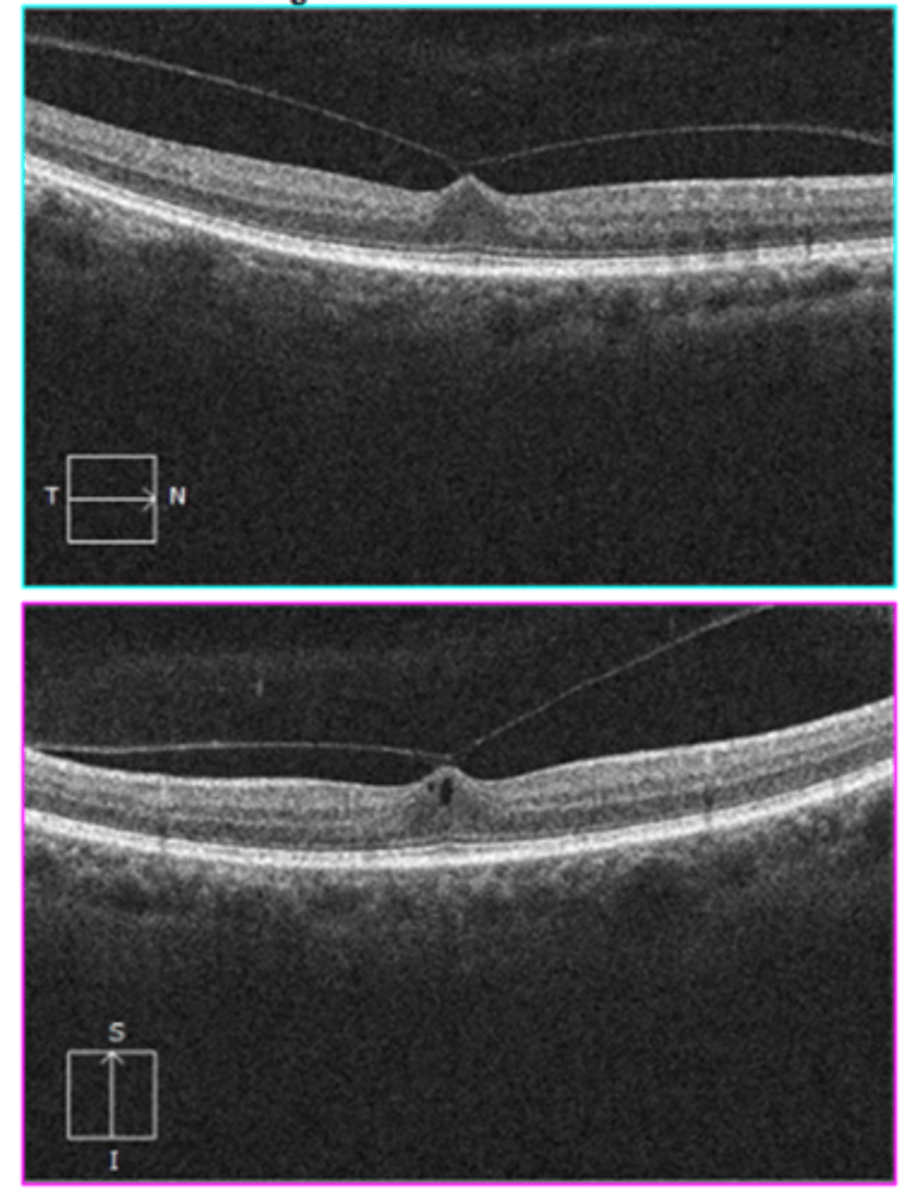

How does a full thickness macular hole appear on OCT, as shown here?

full hole at macula

parafoveal CME

ERM

foveal tissue attached to posterior hyaloid